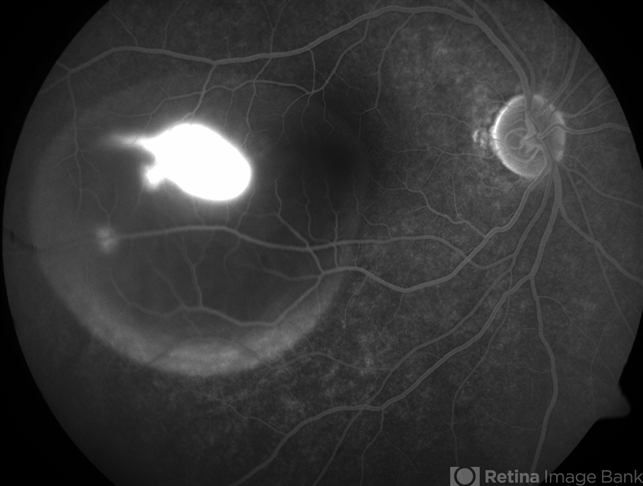

- CENTRAL SEROUS CHRIORETINOPATHY

- central serous chorioretinopathy (CSCR)

- 34-year-old male with right eye CSCR, FFA here shows presence of leaking site which simulates tadpole in the pond.